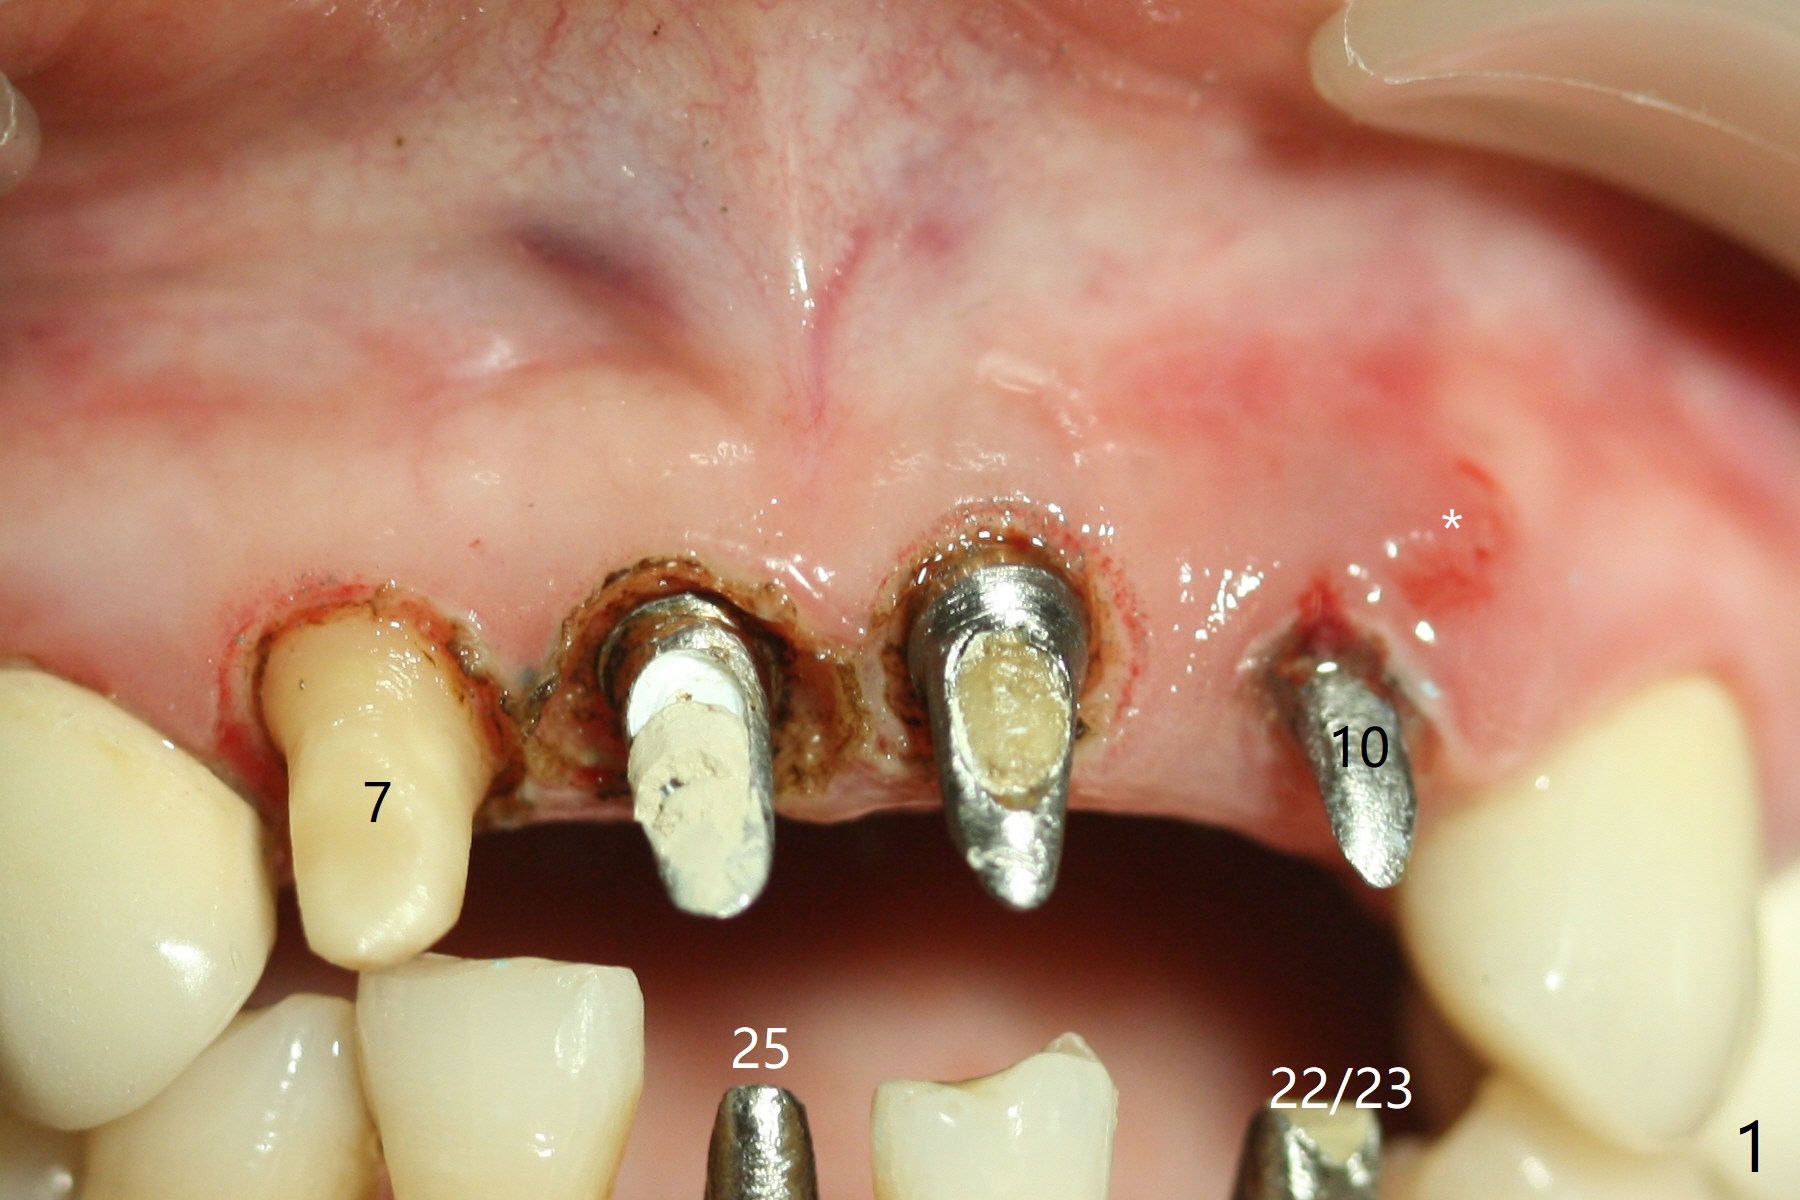

A 45-year-old woman returns for #7-10, 22/23 and 25 restoration; the implant at #10 appears to be inflamed (Fig.1 *). With free hand placement, the implant at #8 seems to be close to the Incisive Canal (Fig.2,3 *), while those at #9, and 10 are buccally placed (Fig.4,5 B). The implant at #10 will be replaced with a smaller one palatally (Fig.6 green). In fact the patient requests #9 implant redo because of protrusive crown.